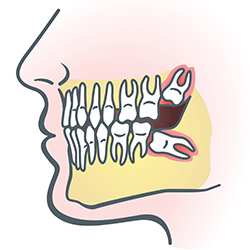

Wisdom teeth are molars found in the very back of your mouth. These teeth usually appear in late teens or early twenties, but they may become impacted (fail to erupt) due to lack of room in the jaw or angle of entry. When a wisdom tooth is impacted, it may need to be removed. If it is not removed, you may develop gum tenderness, swelling, or even severe pain. Impacted wisdom teeth that are partially or fully erupted tend to be quite difficult to clean and are susceptible to tooth decay, recurring infections, and even gum disease.

Wisdom teeth are typically removed in the late teens or early twenties because there is a greater chance that the teeth's roots have not fully formed and the bone surrounding the teeth is less dense. These two factors can make extraction easier as well as shorten the recovery time.

In order to remove a wisdom tooth, your dentist first needs to numb the area around the tooth with a local anesthetic. Because the impacted tooth may still be under the gums and imbedded in your jaw bone, your dentist will need to remove a portion of the covering bone to extract the tooth. In order to minimize the amount of bone that is removed with the tooth, your dentist will often "section" your wisdom tooth so that each piece can be removed through a small opening in the bone. Once your wisdom teeth have been extracted, the healing process begins. Depending on the degree of difficulty related to the extraction, healing time varies. Your dentist will share with you what to expect and provide instructions for a comfortable, efficient healing process.